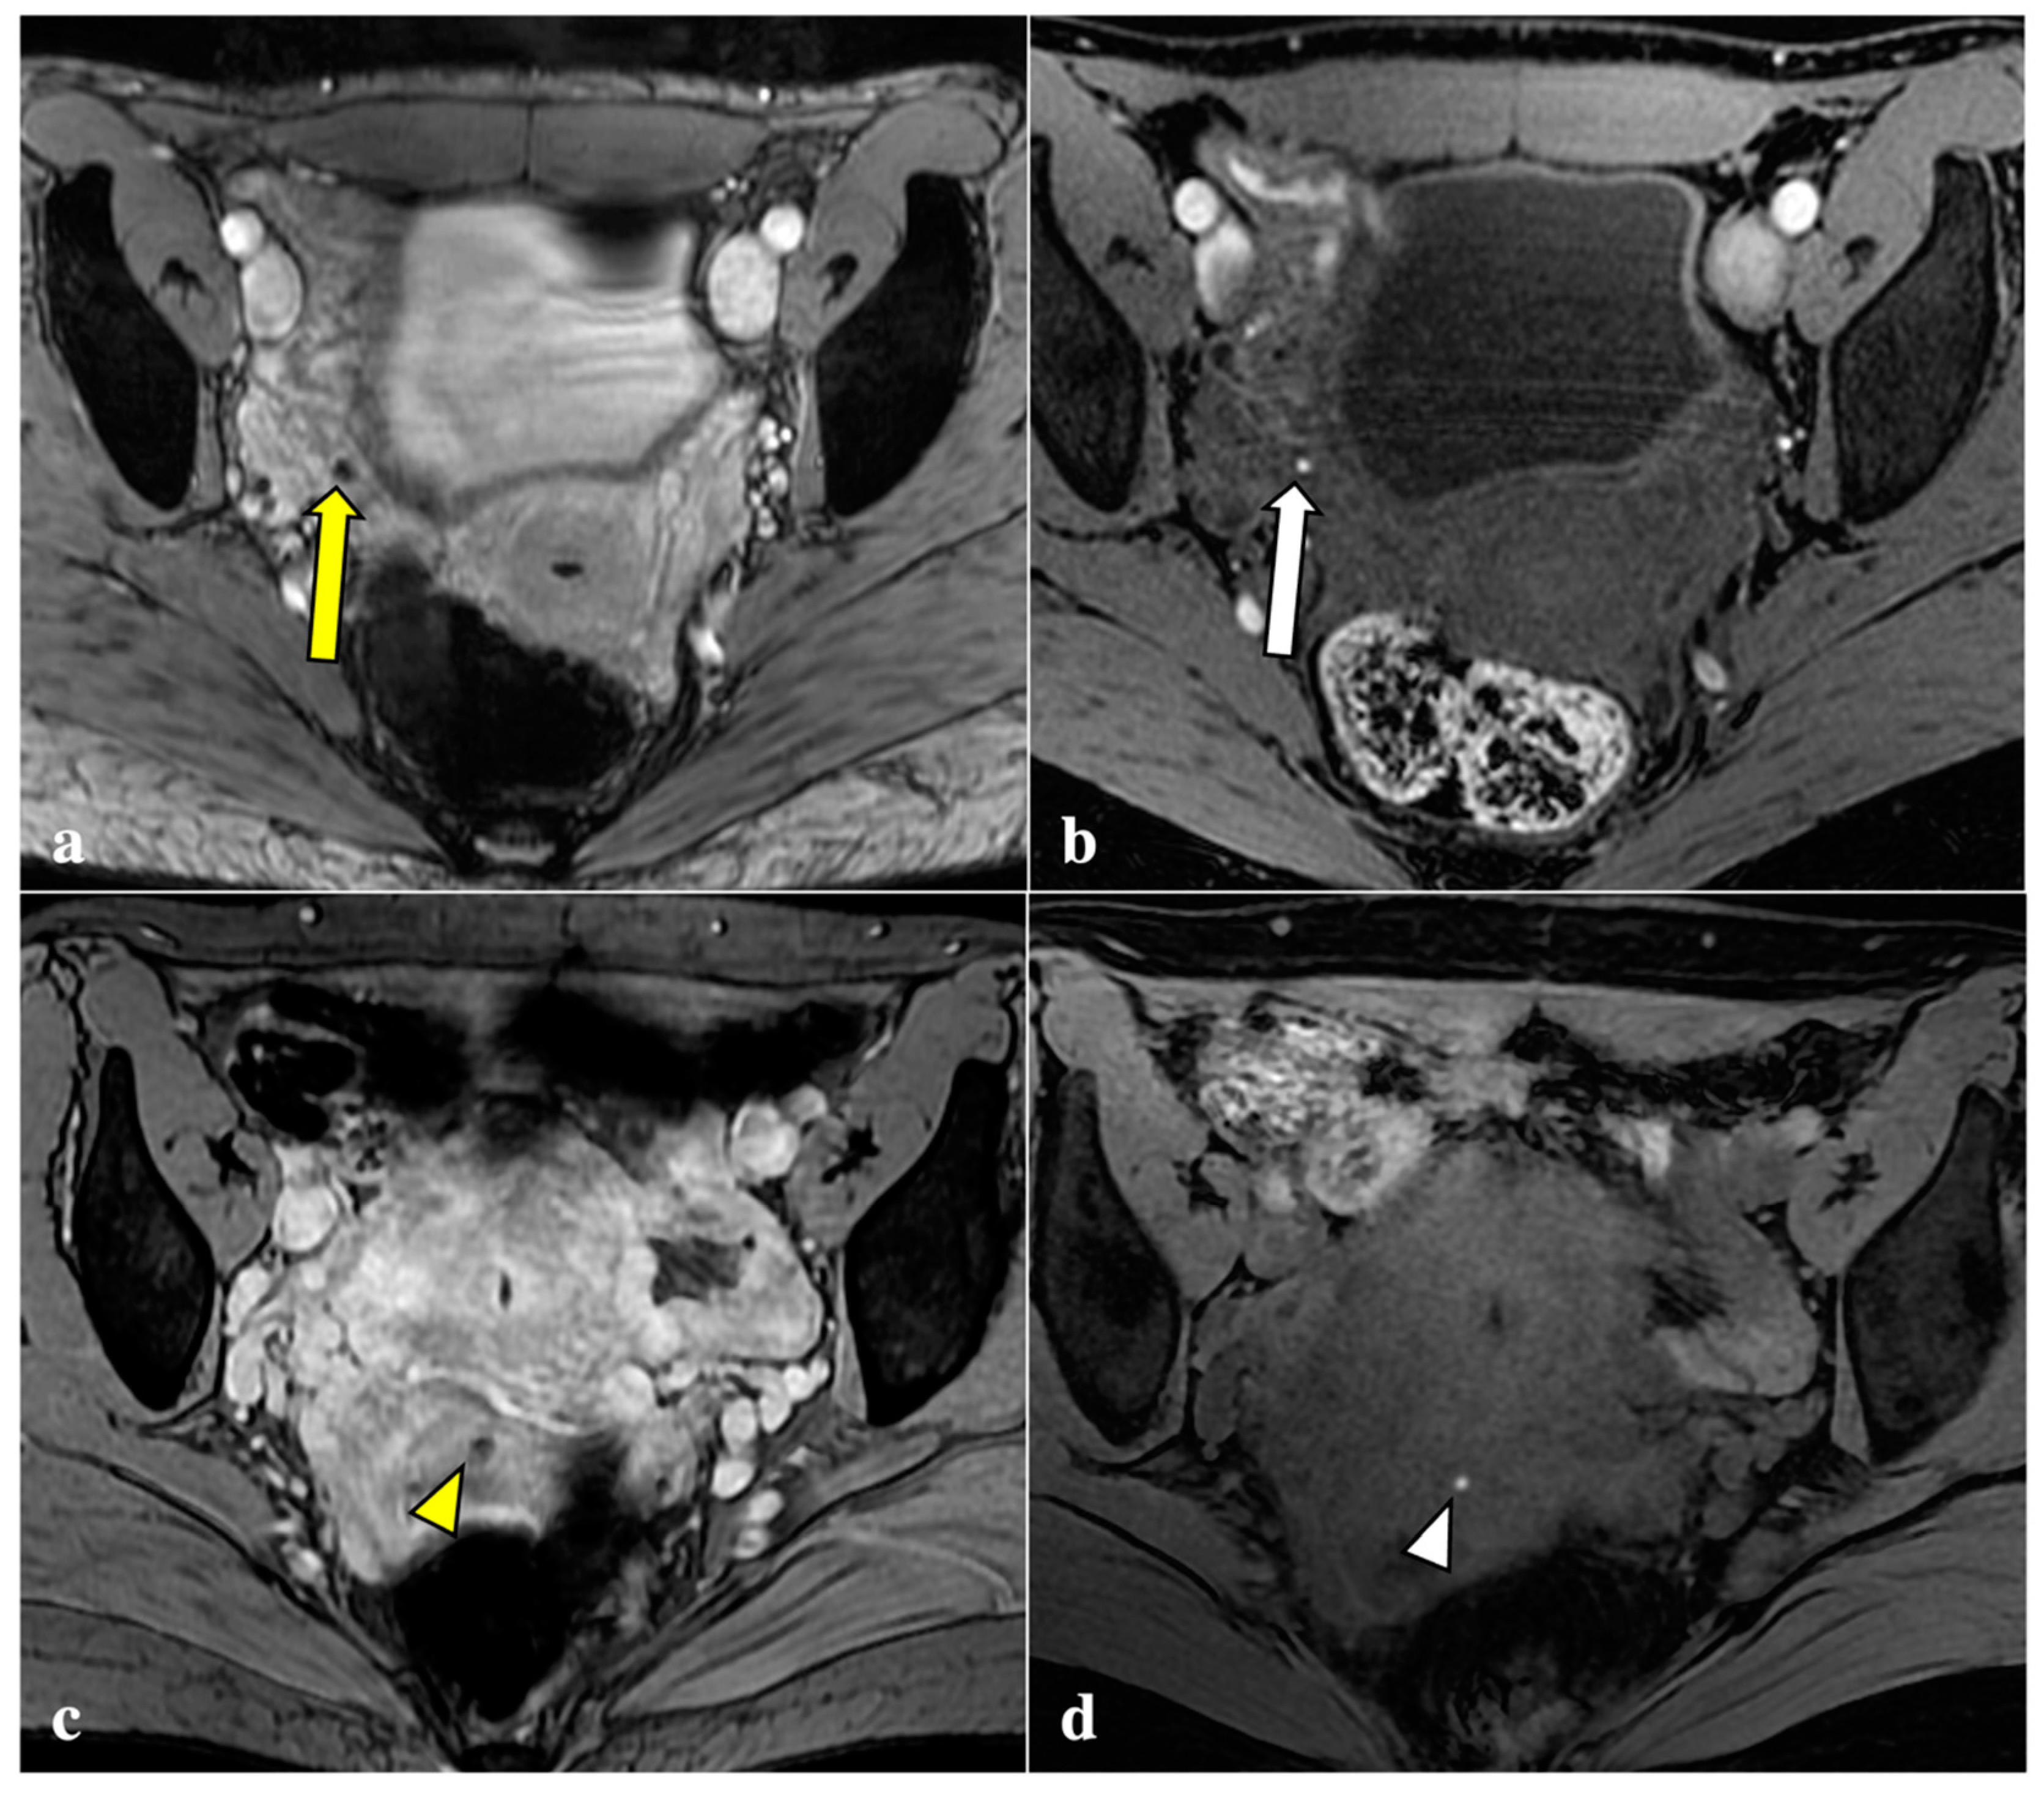

3.2. MRI Findings